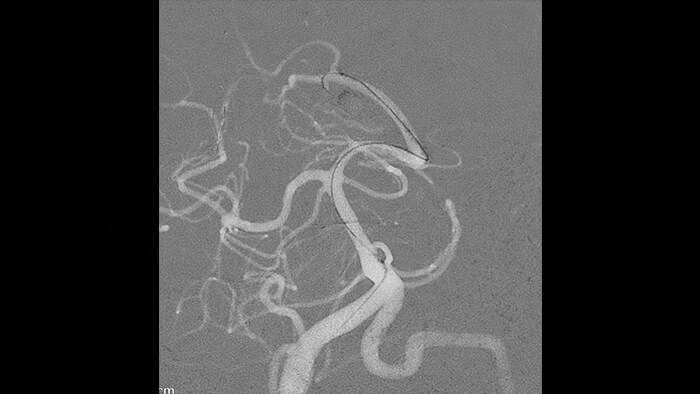

Wenn es darum geht, zu entscheiden, ob ein Patient behandelt oder nur überwacht werden soll, ist es unerlässlich, die besonders komplexen Pathologien der arteriovenösen Malformationen (AVM), von Fisteln und von anderen Malformationen darstellen zu können. Seit Jahrzehnten verlassen sich Neurologen auf die Neurobildgebungslösungen von Philips, um Planungs- und Behandlungsentscheidungen für AVM-Eingriffe zu treffen. Auch jetzt, da nicht rupturierte AVM tendenziell immer häufiger nur überwacht werden, kann unsere spezielle Bildgebungslösung den entscheidenden Unterschied ausmachen.

SmartCT Angio erstellt in wenigen Sekunden eine volumetrische Ansicht, die eine Beurteilung von Versorgungsarterien, Ableitungsvenen, arterialisierten Venen, Nidus und rupturierten oder nicht rupturierten Pathologien ermöglicht und so die Entscheidungsfindung unterstützt. 3D-Volumina und ihre entscheidenden Details werden mit hoher räumlicher Auflösung und automatischer Bewegungskompensation dargestellt.

Die Möglichkeit zur Darstellung der vaskulären Anatomie und endovaskulärer Materialien im Submillimeter-Bereich verbessert die Erfolgschancen und erhöht die Behandlungssicherheit. SmartCT Soft Tissue bietet CT-artige Bilder, die direkt in der Neurovascular Suite erfasst werden und die Identifizierung diskreter Weichgewebeläsionen erleichtern. Eine Kontrolle des Behandlungserfolgs ist somit noch im Untersuchungsraum möglich. SmartCT Vaso bietet 3D-Bildgebung mit hoher Auflösung, die wichtige zerebrovaskuläre Strukturen darstellt und so die räumliche Beurteilung von Gefäßen im Weichgewebe auf besonders hohem Niveau unterstützt.

Bei der Überwachung von AVM über einen längeren Zeitraum können Subtraktionsartefakte klinische Informationen überdecken. Der automatische Pixelshift von Philips ClarityIQ hilft, möglicherweise irreführende Informationen zu entfernen – in Echtzeit und ohne Eingreifen des Benutzers.

ClarityIQ senkt die Patientendosis von Neuro-DSA*-Verfahren bei gleichbleibender Bildqualität um 75 % gegenüber Systemen ohne ClarityIQ und ist so für eine breite Patientenpopulation geeignet. Die automatische Bewegungskompensation von ClarityIQ entfernt Schädel- und Bewegungsartefakte, was bei der Platzierung kleiner Implantate an der Schädelbasis entscheidend ist.